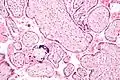

Micrograph of CMV placentitis